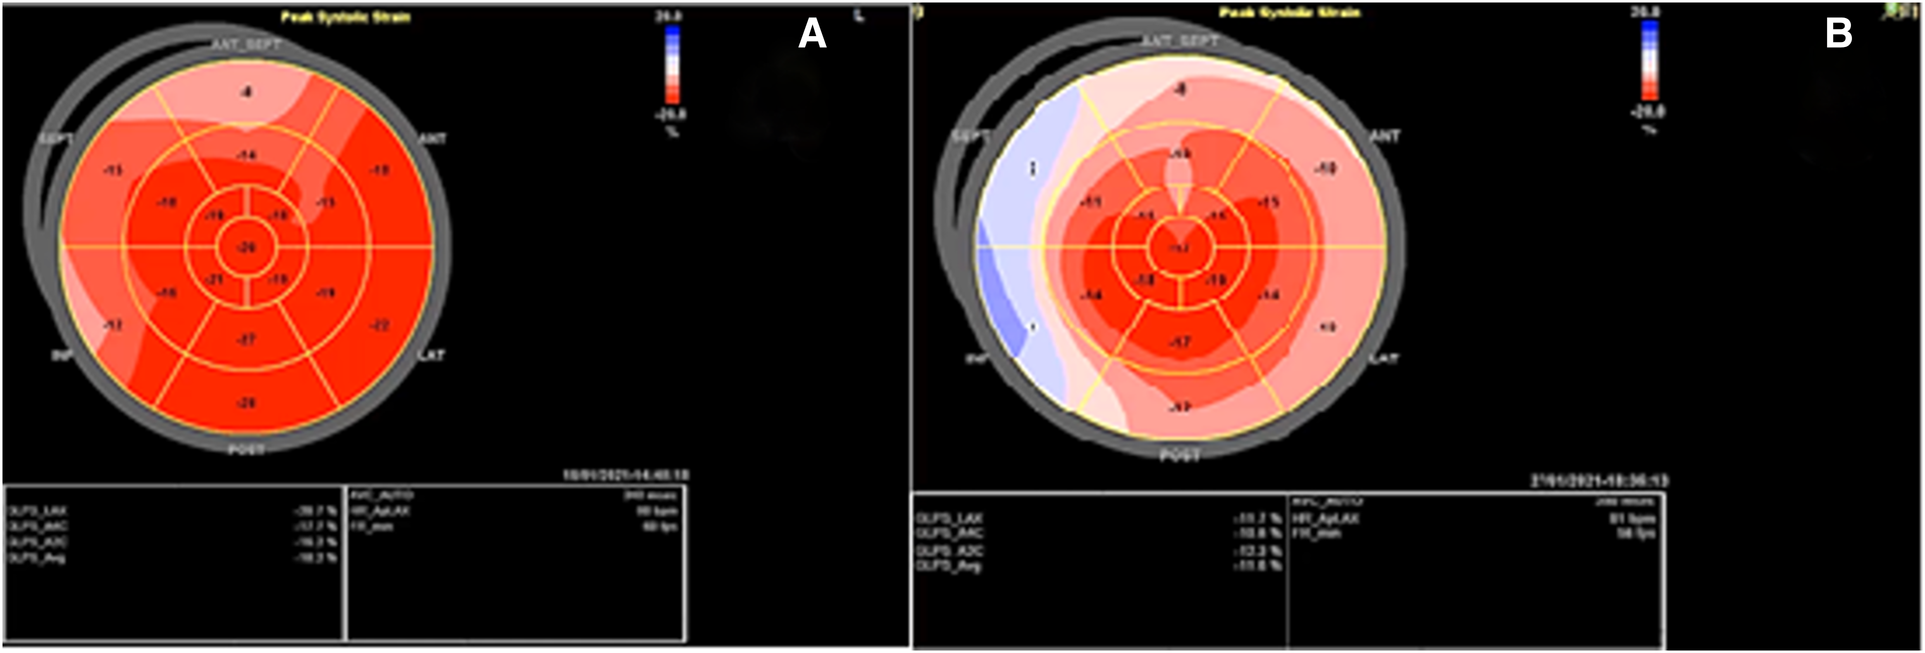

Before mastectomy, TTE evaluation (performed for estimation of surgical risk) showed an LV EF of 42% and a global longitudinal strain (GLS) of −18.2% (Figures 1, 2A) with mild ischemia in the apex on SPECT. Before RT, PVC was 6% in the 24-h ECG Holter monitoring. After RT, the frequency of PVCs during 24-h Holter monitoring raised to 13.8%, accompanied by a drop of LV EF to 29% (from 42%) and GLS to −11.2% (from 18.2%, Figures 2B, 3). LV EF was measured by 2D TTE and was calculated using Simpson's method. She did not receive any course of chemotherapy at all.

Figure 2

Speckle tracking echocardiography before and after the radiotherapy course: (A) Before radiotherapy, which showed a global longitudinal strain of −18.2% with myocardial performance impairment in the bases of inferior, septal, and anteroseptal walls a week. (B) After radiotherapy, which showed GLS: −11.2% with evidence of severe myocardial performance impairment accompanied by relative apical sparing.